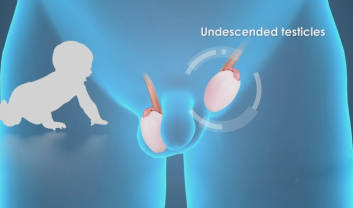

Undescended testis, a condition that may affect newborn males, is a topic that demands our attention. As a concerned parent or individual...